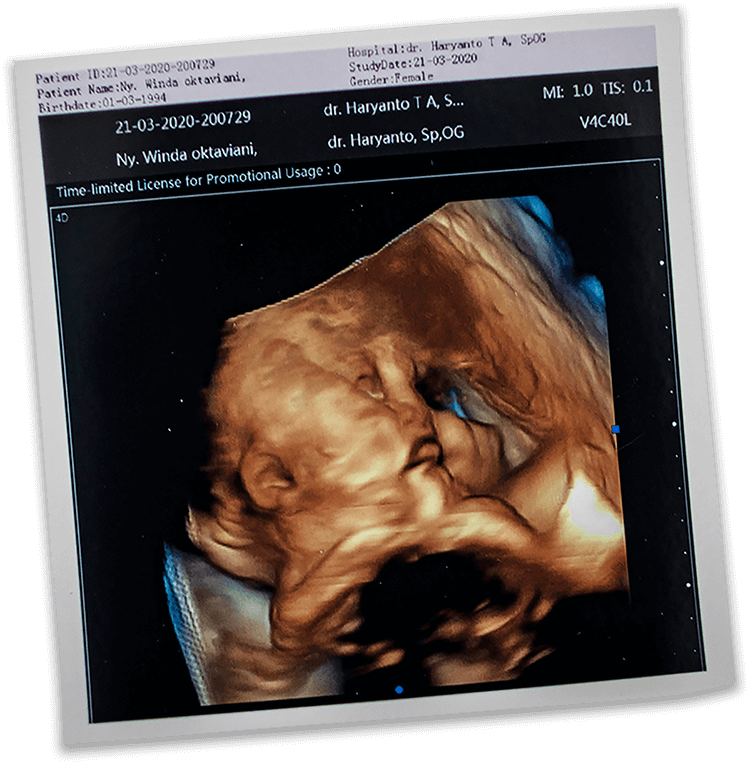

Dan kemudian suara tangis itu muncul. Memecah situasi di ruang bersalin. 6 Mei 2020, pukul 14.53, putri pertamaku dan Okky menyapa dunia lewat tangisan kerasnya.

Amaranggana Kianda Raharjo, kami menamainya.

Amaranggana berarti bidadari. Doa kami agar kelak ia akan menjadi bidadari bagi kedua orang tuanya.